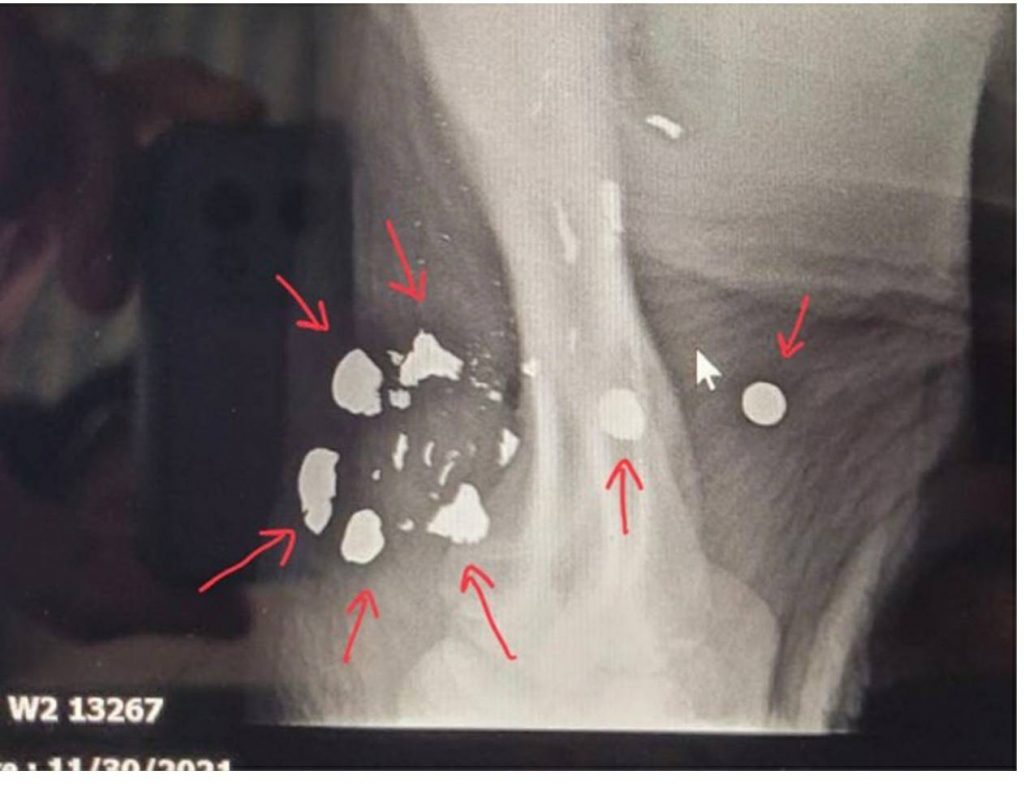

คุณหมอเผด็จกล่าวว่า แผลขาหน้าขวาที่โดนบ่วงรัดนั้น เนื้อตายหมดแล้ว จะต้องตัดออกแล้วขูดเนื้อเพื่อรักษาอาการอักเสบ จากนั้นจะเลเซอร์เพื่อเร่งสร้างผิวหนังมาหุ้มซึ่งจะช่วยลดโอกาสติดเชื้อ รวมทั้งเตรียมทำรองเท้าเสริมส้นให้เพื่อให้เดินได้ ส่วนที่ต้นขาหน้าซ้ายเอกซเรย์พบเศษกระสุนฝัง โดยเป็นชิ้นใหญ่ 9 ชิ้นและชิ้นเล็กๆ อีก 10 กว่าชิ้น เมื่อมาถึงสวนนงนุชต้องประเมินว่า ลูกช้างพร้อมรับยาสลบหรือยาซึมเพื่อผ่าตัดหรือไม่เนื่องจากทิ้งไว้นานจะเป็นอันตราย ขณะนี้อักเสบและบวมมาก โดยตั้งใจจะใช้เครื่องเอกซเรย์ที่ฉายภาพเคลื่อนไหวแบบเรียลไทม์ประกอบการคีบเศษกระสุนออก แทนการผ่าตัดแบบเปิดเนื่องจากลูกช้างยังเล็ก นอกจากนี้ยังเตรียมให้น้องขวากรักกินนมจากแม่รับด้วยซึ่งจะช่วยเสริมภูมิคุ้มกัน หากแผลหายแล้ว ต้องทำกายภาพบำบัดด้วยการว่ายน้ำเพื่อไม่ให้กล้ามเนื้อฝ่อจนไม่สามารถเดินได้.- สำนักข่าวไทย